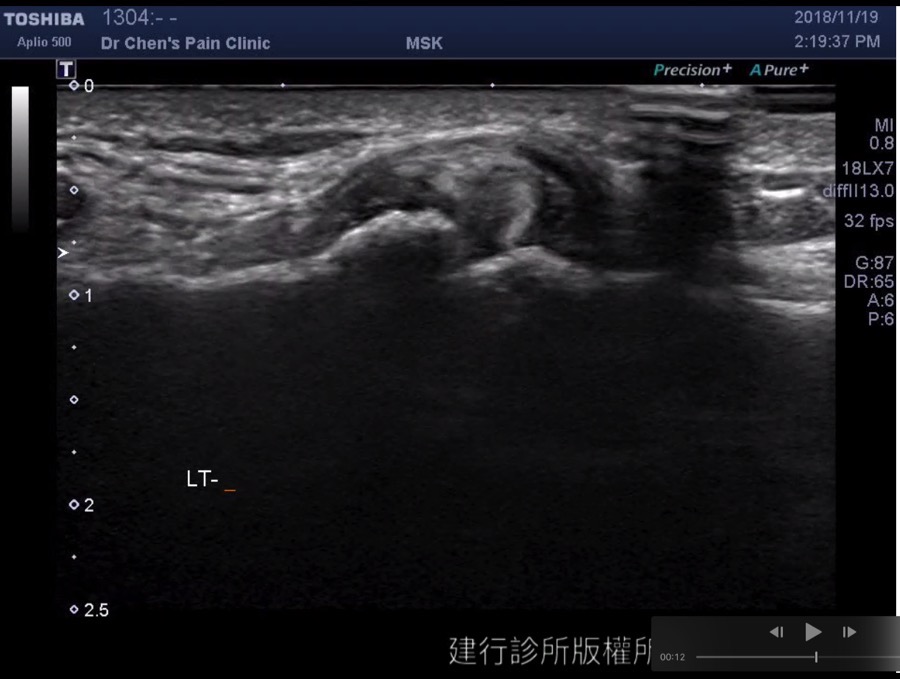

Biceps anchor tendinosis

可以見到二頭肌因為脊上肌肌腱斷裂造成二頭肌往內移動,以及二頭肌肌腱明顯腫大發炎的現象